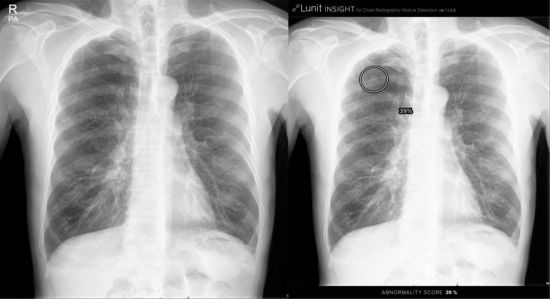

인공지능 기반 영상판독시스템 ‘루닛 인사이트’ 폐암 조기 진단

이번에 활용되는 AI기반 영상판독 보조시스템 ‘루닛 인사이트’는 소프트웨어 개발회사 루닛과 서울대병원 영상의학과 박창민 교수팀이 공동으로 개발에 참여했다. 병원은 루닛 인사이트를 인피니트헬스케어의 의료영상정보시스템(PACS)에 탑재해, 실제 영상판독에 활용한다.

흉부 엑스선 영상은 폐암을 포함한 다양한 흉부 질환의 진단과 평가에 매우 중요한 검사지만, 그 특성상 실제 폐암 같은 중요 질환에 대한 판독 정확도는 높지 않은 단점이 있었다. 루닛 인사이트는 흉부 엑스선 영상에서 폐암 혹은 폐 전이암으로 의심되는 소견을 발견하고 의사의 진단을 보조하게 된다. 양질의 영상 데이터와 독자적인 딥러닝 기술을 이용해, 크기가 작거나 갈비뼈와 심장 같은 다른 장기에 가려져 자칫 놓치기 쉬운 폐암 결절도 정확하게 찾아내는 역할도 한다.

최근 의료영상분야 학술지인 ‘방사선학’에 게재된 서울대병원 연구팀의 논문에 따르면, 이번 AI 소프트웨어 활용 시 흉부 엑스선 폐암 결절 판독 정확도가 영상의학과 전문의가 포함된 연구 대상자 18명의 의사 모두에게서 향상됐다. 이런 성과를 바탕으로 지난 8월 루닛 인사이트는 식품의약품안전처로부터 AI 기반 영상분석 의료기기로 승인받았다.